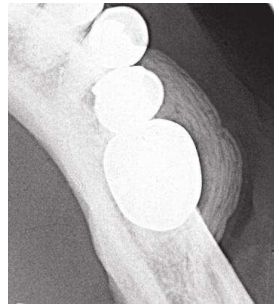

74.下列何種疾病最常造成如圖中洋蔥皮狀骨膜反應之影像? (A)牙骨質骨發育不良(cementa-osseous dysplasia) (B)柏哲德氏病(Paget's disease) (C)平伯氏腫瘤(Pindborg's tumor) (D)加勒氏骨髓炎( Garre's osteomyelitis)